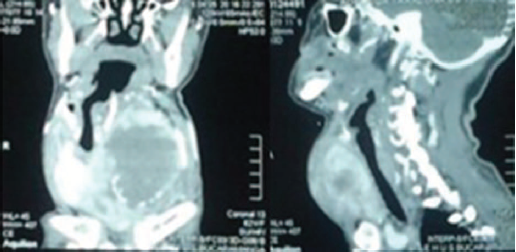

Las tomografías de cuello y tórax reportaron tumor tiroideo y trombosis de vena yugular interna derecha, metástasis pulmonares y en caja torácica. Las dimensiones axiales mayores del tumor eran 9,3x8,7 cm y en el eje vertical 10,2 cm que condicionaban gran desplazamiento lateral derecho de la tráquea, y posterolateral de las estructuras vasculares (Imagen 1). El estudio histopatológico reportó cáncer anaplásico de tiroides grado IV. Las pruebas de función tiroidea evidenciaron hipertiroidismo, por lo cual se inició propanolol.